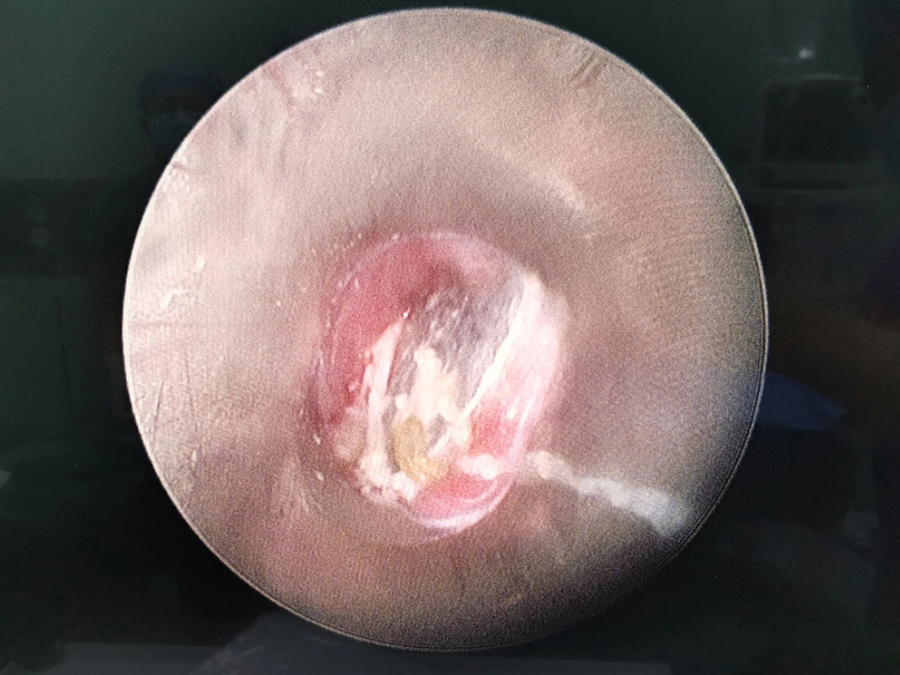

了解了患儿的情况后,国家儿童医学中心、首都医科大学附属北京儿童医院耳鼻喉头颈外科常驻专家、蜜桃视频 副院长张薇仔细看了患儿的X光片,明确了异物的存在和准确位置。由于异物存留时间长,食道是否有肉芽增生、有无穿孔等情况都不明确,张薇副院长决定采用全麻下通过食道镜直视下行异物取除术。

手术非常顺利,当卡在小强食道入口下方的硬币被取出后,家长才知道,原来导致孩子受罪一个多月的竟是一枚硬币。由于硬币卡在食道内时间太长,被取出时颜色已经发黑。术后,小强不能像其他孩子一样迅速恢复呼吸,而是住进了ICU。原来是由于异物坎顿,食道入口关闭不全,小强进食时总会呛咳,导致反复吸入性肺炎,肺功能明显受损,肺内通气量不足、反复发热,全身身体机能下降,所以不能及时苏醒。不过,经过医务人员进一步治疗后,小强现已康复出院。